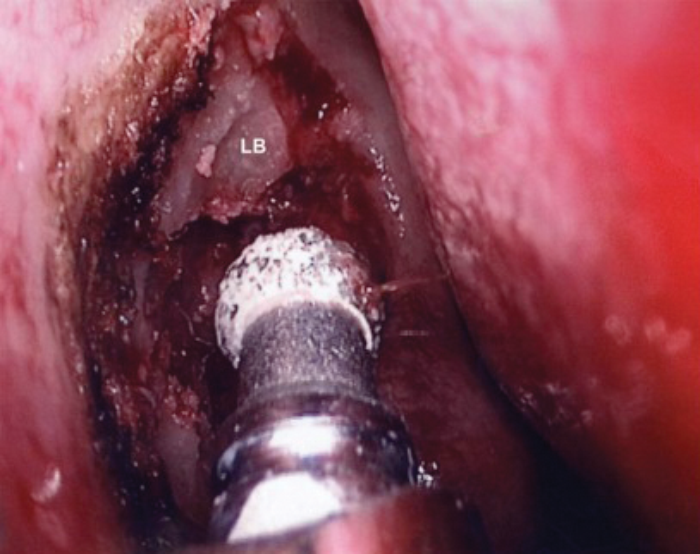

LB - Lacrimal bone

Figure 3. Removal of upper part of lacrimal bone with diamond drill.